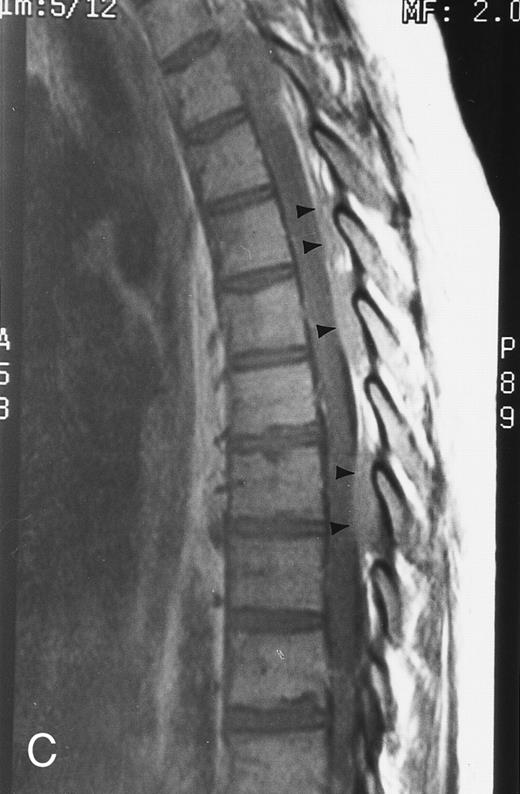

Diffuse MR pattern of abnormal marrow in a 29-year-old man with AML: T1-weighted sagittal (500/10, TR/TE) (A), T2-weighted, fat-suppressed fast spin echo sagittal (5000/96, TR/TE, ET 16) (B), and enhanced T1-weighted sagittal (500/10, TR/TE) (C) MR images of the thoracic spine. The abnormal vertebral bodies in (A) are dark and isointense to the intervertebral discs and in (B) they become bright. In (C), the abnormal marrow enhances and the vertebrae become brighter than the discs. Note extraosseous mass (arrowheads) in the posterior epidural space with preservation of the bony cortex.